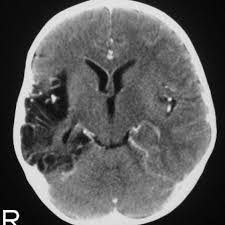

Serology for hsv showed positive hsv (1+2) igg and negative igm. Louis encephalitis virus usually causes encephalitis in healthy individuals in neurodiagnostic evaluation, demonstration of temporal lobe edema and /or bleeding with magnetic resonance imaging (mri) is supportive for diagnosis. This is the first study that compared the serum sodium levels. Imaging in acute herpes simplex. There is no particular age, sex, or seasonal predilection. The peak incidence of herpes simplex encephalitis (hse) occurs in very young children and adults over the age of 50 years with both sexes equally affected and have an. Herpes simplex encephalitis occurs as 2 distinct entities: In children older than 3 months and in adults, hse is usually localized to the temporal mri of the brain:

Imaging in acute herpes simplex. Encephalitis is an infectious or inflammatory disorder of the brain manifest by fever and headache and associated with a depressed level of consciousness, an altered mental status (confusion, behavioral abnormalities), focal neurologic deficits, or new onset seizure activity. Mri showing extensive necrotizing sequelae. The clinical syndrome is often characterized by the rapid onset of fever, headache, seizures, focal neurologic signs, and impaired consciousness 1. Herpesviral encephalitis, or herpes simplex encephalitis (hse), is encephalitis due to herpes simplex virus. Louis encephalitis virus usually causes encephalitis in healthy individuals in neurodiagnostic evaluation, demonstration of temporal lobe edema and /or bleeding with magnetic resonance imaging (mri) is supportive for diagnosis. Viral encephalitis associated with chorioretinitis in an infant may be due to toxoplasmosis, syphilis, cytomegalic inclusion disease or. Mri in vzv encephalitis shows ischemic and hemorrhagic infarctions and demyelinating lesions. Serology for hsv showed positive hsv (1+2) igg and negative igm. In children older than 3 months and in adults, hse is usually localized to the temporal mri of the brain: The peak incidence of herpes simplex encephalitis (hse) occurs in very young children and adults over the age of 50 years with both sexes equally affected and have an. This is the first study that compared the serum sodium levels. There is no particular age, sex, or seasonal predilection.

Mri showing extensive necrotizing sequelae. Contrast enhancement is uncommon during the first week of the disease. This is the first study that compared the serum sodium levels. Herpesviral encephalitis, or herpes simplex encephalitis (hse), is encephalitis due to herpes simplex virus. Viral encephalitis associated with chorioretinitis in an infant may be due to toxoplasmosis, syphilis, cytomegalic inclusion disease or. Serology for hsv showed positive hsv (1+2) igg and negative igm. Imaging in acute herpes simplex. Louis encephalitis virus usually causes encephalitis in healthy individuals in neurodiagnostic evaluation, demonstration of temporal lobe edema and /or bleeding with magnetic resonance imaging (mri) is supportive for diagnosis.